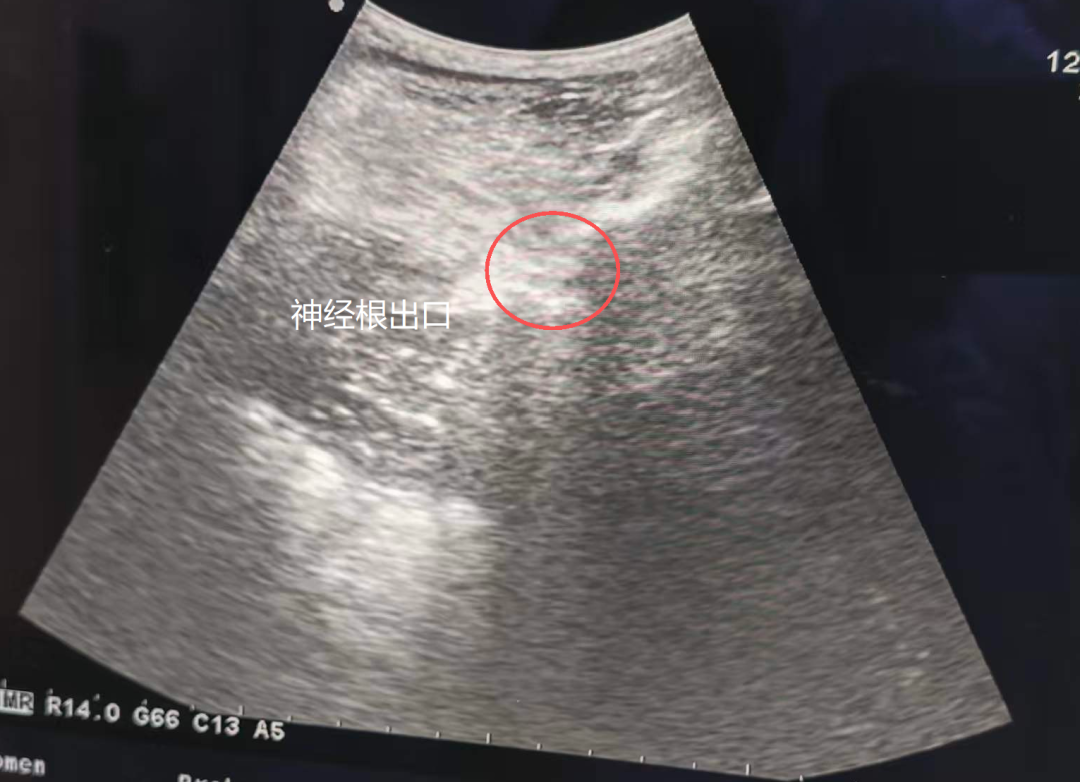

随后,吴树鑫医生为许先生制定了门诊彩超引导下的神经根阻滞治疗,成功解决困扰。